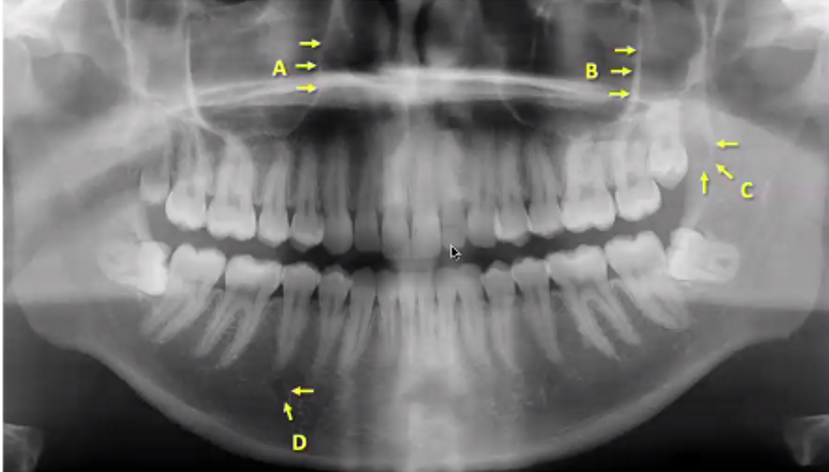

A

inferior alveolar canal (right)

B

left coronoid process

C

left external auditory meatus

D

left hyoid bone